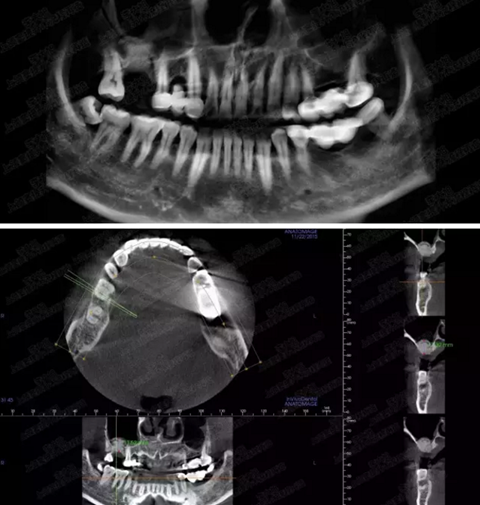

病例三

剩余骨量3mm

005.png

006.png

病例四

剩余骨量2mm-5mm且存在斜形竇底

007.png

提升8mm

008.png

009.png